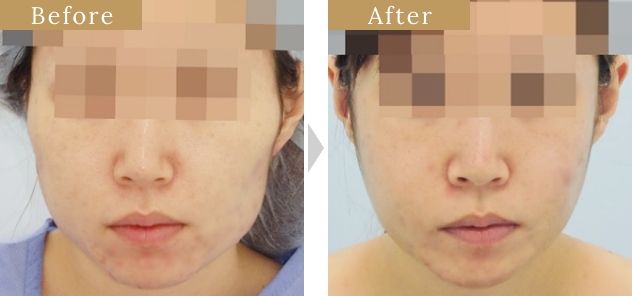

症例